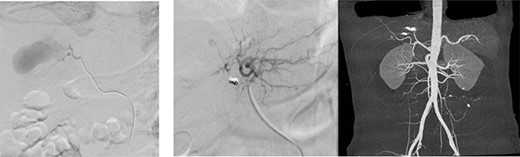

After 1 week of embolization, a follow-up CT scan detected thrombosis of the lateral segmental branch of the left portal vein. Prophylaxis dose of heparin was increased to the therapeutic range and, a week later, duplex US examination was performed, which documented the resolution of this thrombosis. The patient was transferred to the rehabilitation care on daily oral aspirin. A repeat CT scan was done after 1 month in which no pseudoaneurysm was seen, with normal flow in the hepatic arteries and portal vein (Fig. 7). During the following 2 months, the patient remained asymptomatic and was discharged home without complications.

Repeated CT scan of the abdomen after 4 weeks revealed partial healing of the liver injury with disappearance of the pseudoaneurysm.